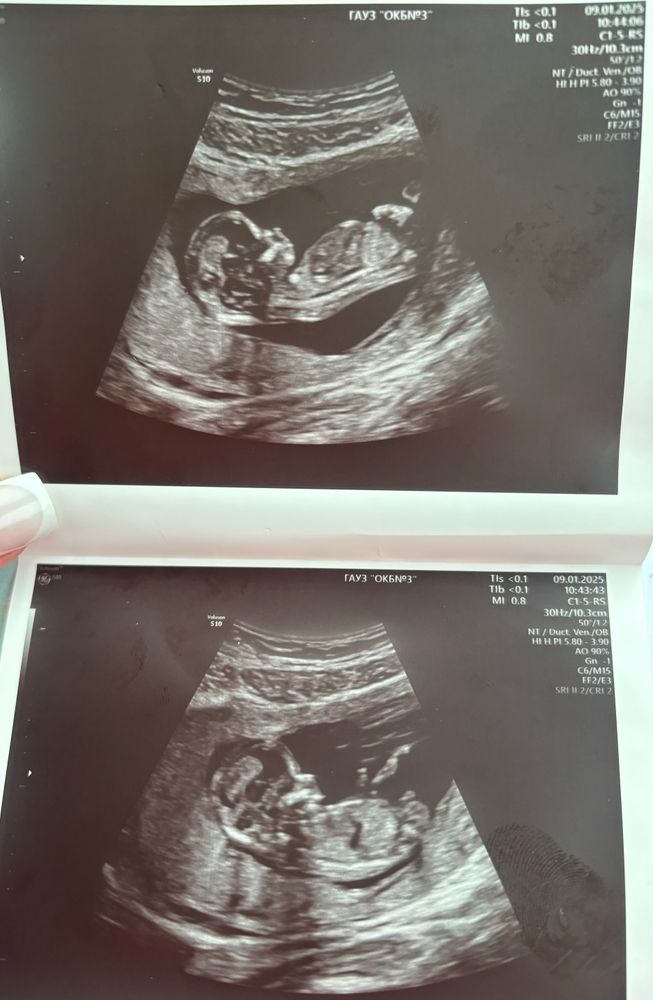

Мы были на скрининге 3 января в ОПЦ на Тимирязева, срок по узи 13.3. Нам доктор сам предложил узнать пол) у нас девочки. А вообще вот очень информативно расписано мне кажется https://www.budumamoi.ru/uzi_development.html На таком сроке получается смотрят на угол наклона гениталий.

Я не разбираюсь, но на фото нижнем так удачно как будто писулек видно. Кто бы ни был, главное чтоб здоровый! Легкой вам беременности и родов в срок!

Мне кажется, что мальчик)

Яички так хорошо видно☺️

Мальчик